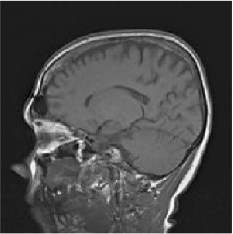

From the above discussions, we have discovered the significant potential of applying Retinex theory to image segmentation and explored its fundamental differences from traditional models. Traditional image segmentation models typically focus on the impact of intensity information on the segmentation results. Therefore, when faced with complex segmentation scenarios, the segmentation results are often affected by lighting, artifacts, and unclear boundaries in the image. As shown in Fig. 1, we present the results of the classical local model LIF [ZHANG20101199] for segmenting brain tumor images along with surrounding tissue edema. The irregular ring-like enhancement caused by the edematous tissue leads to irregular boundaries and low contrast in the images. Consequently, the LIF model can only identify the central necrotic and liquefied regions of the tumor, failing to detect the boundaries and becoming trapped in local minima. In this paper, we draw inspiration from the Retinex theory, which is widely applied in the field of image enhancement. According to Retinex theory, the reflectance component characterizes the intrinsic structural properties of the observed image and preserves texture information independent of illumination variations. By integrating this reflectance component into the level set framework, our model achieves robust segmentation of medical images even under severe intensity inhomogeneity. In addition, a linearized Structural-Prior is proposed to restore intensity consistency and capture local geometric features, thereby improving boundary localization in complex or blurred regions. Furthermore, a relaxed binary level set representation is employed to enhance robustness against noise and to enable accurate tracking of complex contours. Based on these innovations, we propose a novel variational reflectance-based level set model (RefLSM) that simultaneously corrects bias fields and performs segmentation. Experimental results demonstrate that RefLSM significantly outperforms conventional level set methods in both segmentation accuracy and robustness. We present the results of our model segmenting the two brain tumor images mentioned above in Fig. 2.